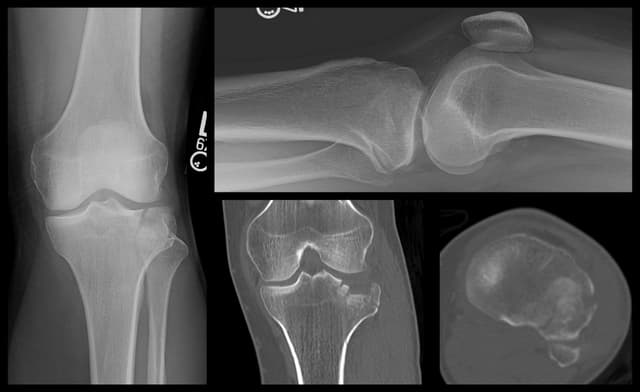

Imaging

Pre-op